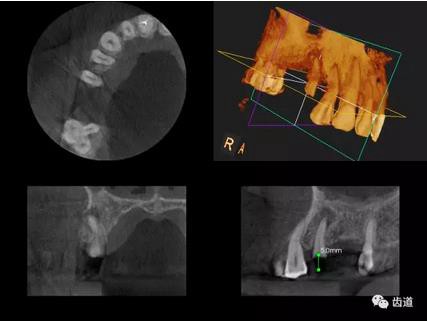

三)種植修復(fù)

CBCT在牙種植修復(fù)中的應(yīng)用。種植前利用CBCT對患者的牙床進行檢查,可精準(zhǔn)判斷牙槽骨的寬度、厚度及高度、骨的密度、重要的顏面神經(jīng)、血管和鼻竇位置等。臨床醫(yī)生不僅可以在計算機直觀的看到牙槽骨的立體影像,還可以切換不同的視角來觀察硬組織之間的位置關(guān)系,在手術(shù)方案中避開危險區(qū)域,保證手術(shù)的安全性。臨床醫(yī)生還可以利用CT數(shù)據(jù)進行數(shù)字模型重建,配合軟件預(yù)先做好手術(shù)模板,使種植手術(shù)更安全快捷,避免在種植手術(shù)過程中不慎破壞神經(jīng)、鼻竇等解剖結(jié)構(gòu),導(dǎo)致顏面神經(jīng)麻痹、鼻竇炎等并發(fā)癥的發(fā)生。

1、下頜骨種植牙前測量準(zhǔn)備影像

2、上頜骨種植牙前準(zhǔn)備影像